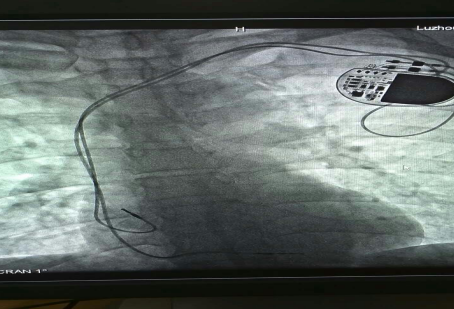

已安裝好的起搏系統(tǒng)

在征得患者及家屬的同意后,我院為其實施了雙腔永久心臟起搏器植入術(shù),該手術(shù)在瀘州市市屬醫(yī)院中率先使用磁共振兼容起搏電極,為患者未來有可能接受的磁共振檢查創(chuàng)造了條件。